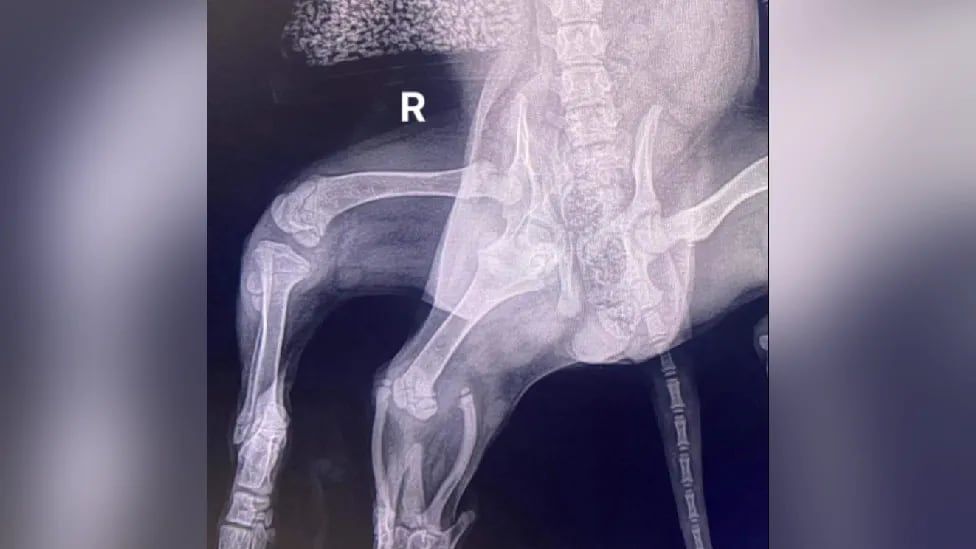

Ariel, que recibió su nombre del personaje de “La Sirenita” porque las dos patas en el extremo parecía una aleta, corrió por el pasto el sábado mientras se adapta a la vida en cuatro patas tras una importante cirugía.

Las patas sobrantes salían del cuarto trasero derecho y parecían inútiles, colgando junto a su cola que se movía, mientras caminaba un poco torpemente en un vídeo grabado antes de la operación, informó la agencia AP.